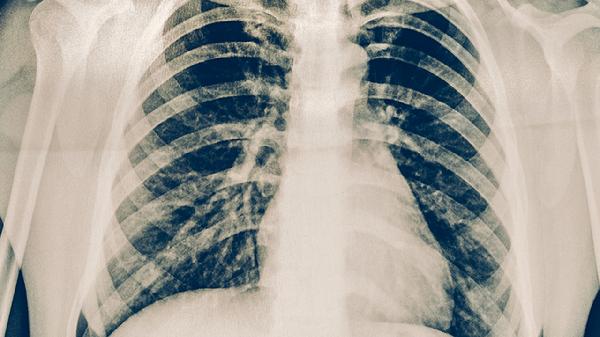

中医治疗肺结核需坚持3个月以上,期间定期复查胸部影像学。治疗期间应保持居室通风,避免劳累。饮食宜清淡富含蛋白,如鸡蛋羹、鱼肉等。若出现咯血量增多、持续高热等急症,须立即结合西医抗结核治疗。中西医协同干预可提高疗效,但须在专业医师指导下进行。